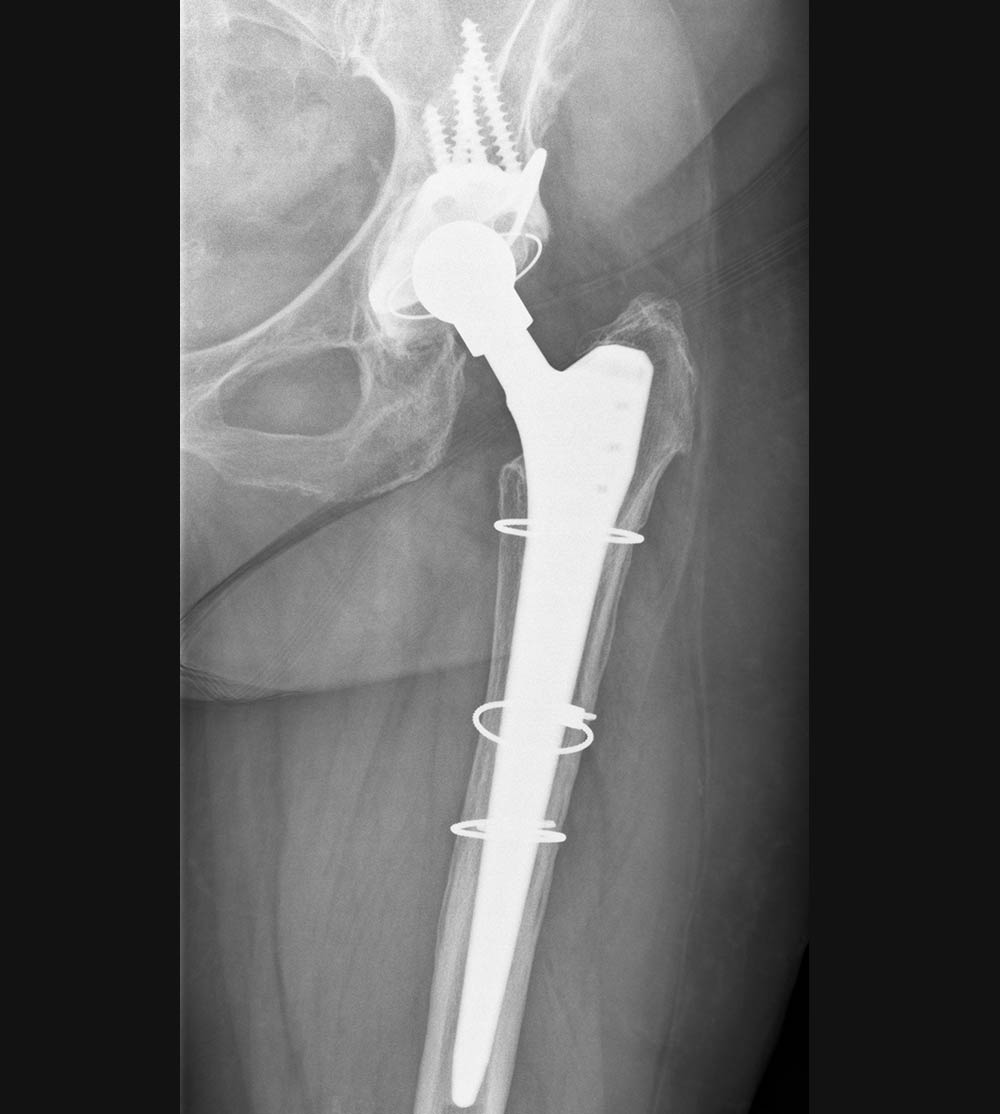

Hüfte

Röntgenbild Pfannenlockerung

Röntgenbild Zustand nach Wechseloperation mit Pfannendachschale

12 Jahre nach Wechsel einer Hüftprothese

12 Jahre nach Wechsel einer Hüftprothese